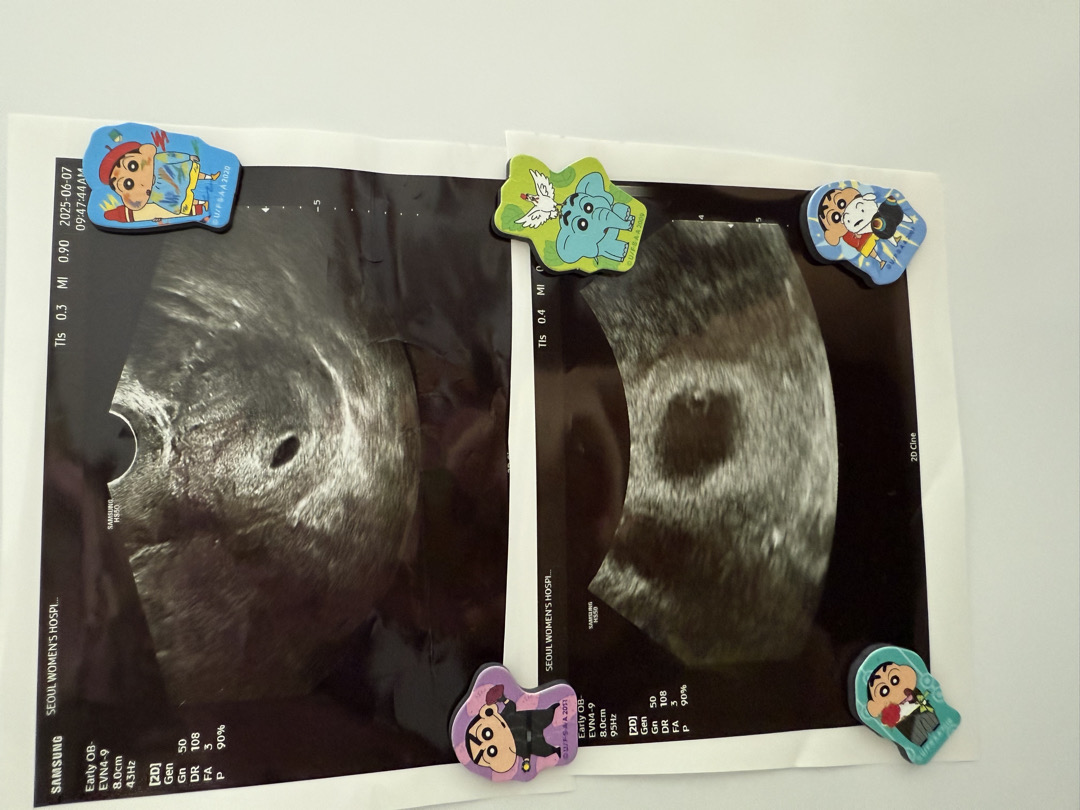

위에껀 5주차 막들어왔을때 첫 초음파 사진이구요 두번째꺼가 5주6차 오늘초음파 사진입니다 원래는 담주에 와서 심장소리도 듣자고 예악하고 갔었는데 전에 진료 보자마자 다음날부터 오늘까지 연속4일간 갈색냉이 소량 나오다 안나오다 이래서 불안한 마음에 갔습니다!(+명치가 위산과다분비?역류 할때처럼 엄청 답답하고 아프고 그래서 죽만먹기도함)그래서 여럼으로 걱정되서 갔는데 걱정했던건 그냥 애기집이 확장공사하면서 모세혈관이 터져서 소량이 나올수 있다 하셨고 그기간도 언젠간 멈춘다도 하더라구요 우리아이 덕분에 임산부가 짜먹을수 있는 위산약도 처방받고 난황도보고 저쩜같은 쥐똥이 심장이라고 깜빡 거리는 모습도 보고 왔습니다!!너무 신기하더라구요! 너무 작아서 담주에 예정일때 심장소리제대로 듣자고 하셨습니다. 생각보다 빠르게 변화가 되서 놀랍네요 인체가참..다들 첫심장소리 들으면 눈물날까요?전 날꺼 같아요..뿌앵